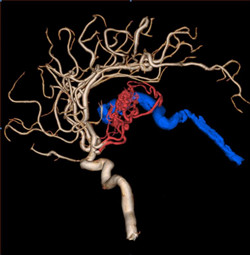

【优势二】自动提取供血动脉,血流量化评估,瘘血管三维精显,AVM智能三维导航。

脑血管畸形是脑血管先天性发育异常,其中动静脉畸形最常见,即是由一团动脉、静脉及动脉化的静脉(动静脉瘘)样血管组成,脑血管发育障碍引起的局部血管数量和结构异常,并对正常脑血流产生影响。临床上常表现为反复的颅内出血、部分性或全身性癫痫发作、短暂性脑缺血发作和进行性神经功能障碍,也是引起颅内蛛网膜下腔出血的第二位病因。

▲典型的脑动静脉畸形,

红色的为供血动脉及畸形血管团,蓝色的为粗大的引流静脉。

如果脑动静脉畸形没有位于重要功能区,不是巨大脑动静脉畸形,一般可通过外科手术、介入治疗或放射治疗治愈。介入治疗就是通过血管内途径,将一根很细的导管(直径<0.5mm)在X线下小心插入到动静脉畸形团内,然后注射一种液体胶将畸形团封闭,防止畸形团再次破裂出血。